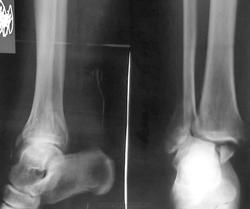

Пациентке 50 лет, в марте 2011 получила бытовую травму, при поступлению в одну из ЦРБ Нижегородской области был диагносцирован трехлодыжечный перелом, наружный подвывих стопы (рентгенограммы 1). Поскольку боковая рентгенограмма сделана с ротацией, никто не обратил внимания на передний отдел метаэпифиза б/берцовой кости. Пациентке налажено скелетное вытяжение (рентгенограммы 2,3), на боковом снимке видно повреждение переднего отдела метаэпифиза, но внимание на это не обращается, выполняется стандартный остеосинтез наружной и внутренней лодыжек (рентгенгограммы 4), опять же ни о кого не возникает никаких вопросов, а именно: почему дисконгруэнтна суставная щель, стопа в переднем подвывихе и в эквинусе. В августе пациентка приходит на контроль, и уже отчетливо виден дефект переднего отдела метаэпифиза б/берцовой кости, смещение костного фрагмента метаэпифиза кпереди и передний вывих стопы, но никаких мероприятий не проводится. Вчера, 9.02 пациентка все же доходит до нашего института, и мы видим такую картину (рентгенограммы 5,6): дефект переднего края дистального метаэпифиза б/берцовой кости, костный фрагмент смещен кпереди, некротизирован (фактически это секвестр), стопа в положении переднего вывиха, разрыв дистального межберцового синдесмоза, нестабильность металлоконструкций в б/берцовой кости (отчетливо видна резорбция), асептический некроз блока таранной кости. Прогноз неблагоприятен: артродезирование г/стопоного сустава, вопрос только в выборе метода, аппаратный артродез, либо ретроградный интрамедуллярный.